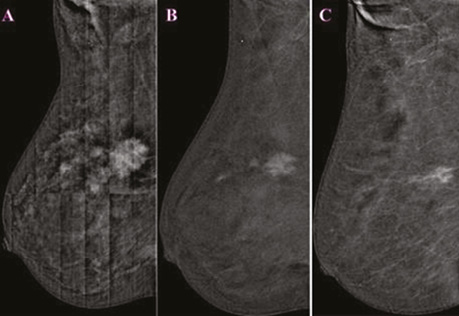

Після 8 курсів НХТ за допомогою СЕМ візуалізувалися лише 2 з 5 вузлових новоутворень зі зниженою інтенсивністю, щільністю фіксації контрасту в динаміці. За допомогою УЗД відзначалося зменшення розмірів пахвових лімфатичних вузлів (рис. 10, 11).

Рис. 10. СЕМ на фоні НХТ в R-CC-проєкції: первинне дослідження (a), контрольне дослідження після 4 курсів НХТ (b), контрольне дослідження після 8 курсів НХТ (c)

Рис. 11. СЕМ на фоні НХТ в R-MLO-проєкції: первинне дослідження (a), контрольне дослідження після 4 курсів НХТ (b), контрольне дослідження після 8 курсів НХТ (c)